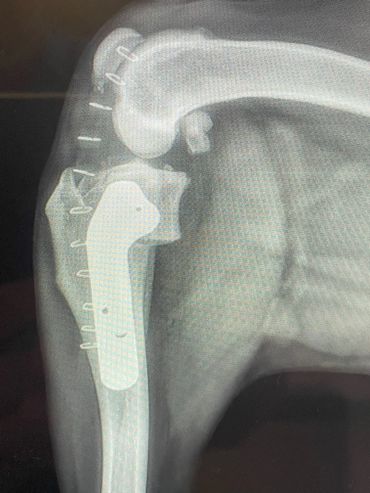

If your pet has a torn CCL they will usually be uncomfortable and manifest this as limping. They often prefer to limit their own activity level due to the pain and may be more sedentary. When a CCL tear is diagnosed, usually the best option is to stabilize the stifle surgically for the best outcome. One technique commonly performed for decades has been the Tibial Plateau Leveling Osteotomy (TPLO). The TPLO was designed to eliminate the tibial thrust motion that occurs with a CCL tear and thus return stability to the stifle for return to function. The TPLO procedure is very technical and thus is best performed by experienced surgeons. Initially the TPLO was only taught by the original designer of the procedure, Slocum Enterprises, and luckily Dr. House managed to complete this training program before it ended. To perform a TPLO procedure a bone cut (osteotomy) is made in the shin bone (tibia) near the knee. This cut is curved and allows a change in the angle within the stifle to alter the forces as mentioned above. Once the cut is made and the bone is rotated, a metal plate and screws are placed to hold the bone in its new position while it heals. These implants are usually left in place for life and are only removed if a reaction or infection should develop, which is generally uncommon. Since a cut is made in the bone for this procedure, patients must go through a rest period while the bone heals adequately for normal activity again. It is critical that patients rest to avoid breaking their bone or the implants. The post-operative instructions typically followed are below. If your pet has been diagnosed with a CCL tear, a TPLO may be recommended. This procedure is usually best performed in pets weighing 50 pounds and above. It can be performed in animals under 50 pounds, however, and this can be determined at a surgical consultation. Dr. House performs the TPLO procedure almost daily and would be happy to meet with you and your pet to discuss and perform the procedure accordingly at your local veterinary clinic.